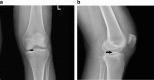

Tibial eminence avulsion fractures are not infrequent in the pediatric population; however, they are rare in the adult population. These injuries typically occur in skeletally immature patients between the ages of 8 and 14 years. We report the unique clinical history, imaging findings, and operative results of a 48-year-old female who presented with severe knee pain. Imaging findings revealed an anterior tibial eminence fracture with an intact anterior cruciate ligament tendon attached to the avulsed fragment. The patient underwent knee arthroscopy, with direct repair of the tibial eminence fracture.